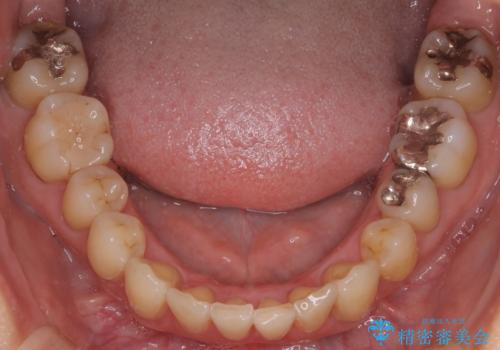

患者様にしっかりとインビザラインを使用して頂けたことで綺麗な仕上がりとなりました。